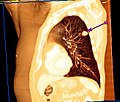

Der Unterschied zwischen der überlagerungsfreien Darstellung in der medizinischen Tomografie und einer Projektionsabbildung ist in den nachfolgenden Abbildungen illustriert. In Projektionsverfahren wie der Radiografie (gewöhnliche Röntgenuntersuchung) wird ein Schattenbild aufgenommen, auf dem sich mehrere Strukturen überlagern, wenn sie im Strahlengang hintereinander liegen. Beispielsweise überlagern beim konventionellen Röntgenbild die Weichteile der vorderen und hinteren Brustwand und die knöchernen Strukturen des Thorax die Lungenstrukturen. Dies würde die Diagnose eines Lungentumors (z. B. Bronchialkarzinom) erschweren. Jedes CT- oder MRT-Schnittbild vom Thorax zeigt dagegen nur eine 0,5 bis 10 mm dicke Schicht, die praktisch überlagerungsfrei ist.

Röntgenbild (Projektionsbild) eines kleinen peripheren Bronchialkarzinoms im linken Oberlappen -

Derselbe Tumor in der Computertomografie (axiales Schnittbild) -

Aus den CT-Einzelschichten zusammengesetztes 3D-Bild